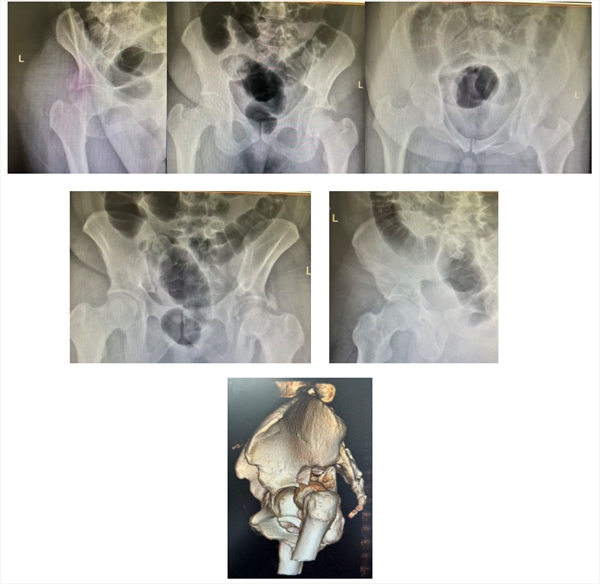

(入院时术前X线及CT三维重建结果:髋臼骨折伴脱位)

患者小曹(化名),年仅26岁,体重达240斤,因车祸被紧急送至望京医院。经检查,被诊断为极为复杂的“髋臼T型骨折伴股骨头脱位”。

髋臼,是骨盆侧壁那个精密的碗状凹陷,它与股骨头共同构成承载人体上半身重量的核心“承重轴碗”。此类骨折多由车祸、高处坠落等高能量暴力导致,股骨头像一把“重锤”,瞬间将这个“碗”砸碎。在骨科领域,国际上普遍采用Judet-Letournel分型来评估其复杂性,而“T型骨折” 正是其中最复杂、最难处理的类型之一——仿佛这个承重碗先被横着砍裂,再被竖着劈开,形成一道残酷的“T”形裂痕,整个结构分崩离析,稳定性尽失。